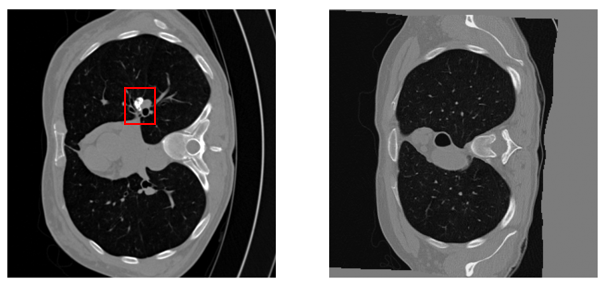

Refer to caption

Fig. 1: Longitudinal LDCT pair. (Left) Follow-up (FU); (Right) Registered baseline (BL_reg). Differences in reconstruction and residual misalignment can destabilize temporal subtraction Δ\Delta, motivating quality-aware fusion.